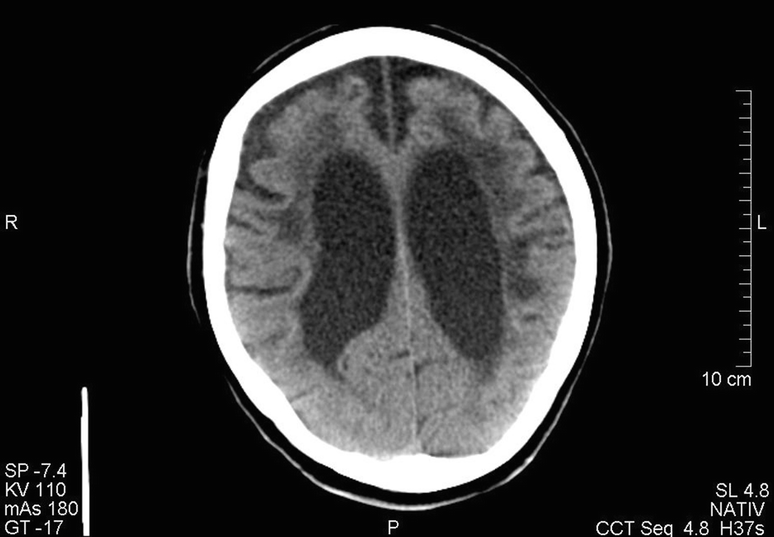

Abb 1 Ct Einer 90 Jahrigen Patientin Mit Einem Ausgepragten

Dementia causes problems with memory thinking behavior language skills and decision making. Brain imaging procedures your doctor may recommend to help diagnose vascular dementia include. Mit ct oder mrt sind bei diesen patienten sehr charakteristische aufgeblähte liquorräume zu sehen. It is primarily seen in patients with atherosclerosis and chronic hypertension and results fr.